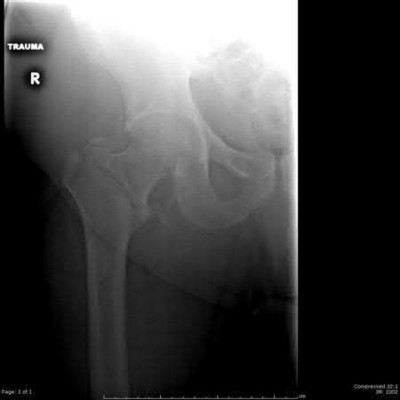

A 12-year-old obese male presents with left knee pain and an antalgic gait. Physical examination reveals an obligate external rotation of the left hip as it is passively flexed. Radiographs confirm a displaced Slipped Capital Femoral Epiphysis (SCFE) on the left.

Prophylactic percutaneous pinning of the contralateral (asymptomatic) hip is most strongly indicated if the patient has a history of which of the following conditions?

Explanation

Prophylactic pinning of the contralateral hip in SCFE is controversial but is generally strongly recommended in patients with an underlying endocrinopathy or metabolic bone disease (e.g., hypothyroidism, renal osteodystrophy, growth hormone deficiency), as well as in patients presenting at an unusually young age (often defined as <10 years old). These patients have an extremely high risk (up to 100% in some metabolic conditions) of developing a contralateral slip.